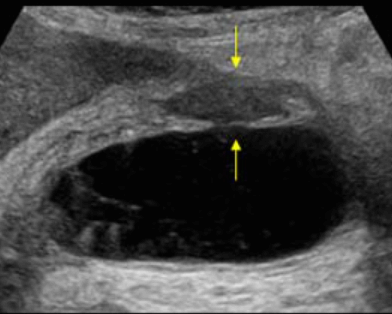

US finding

- 담낭주위 띠모양의 경계가 좋은 액체저류가 보인다

- 담낭은 경계가 불분명해지며 팽팽해진다

- 심한 경우 저에코성 종괴들이 관찰된다